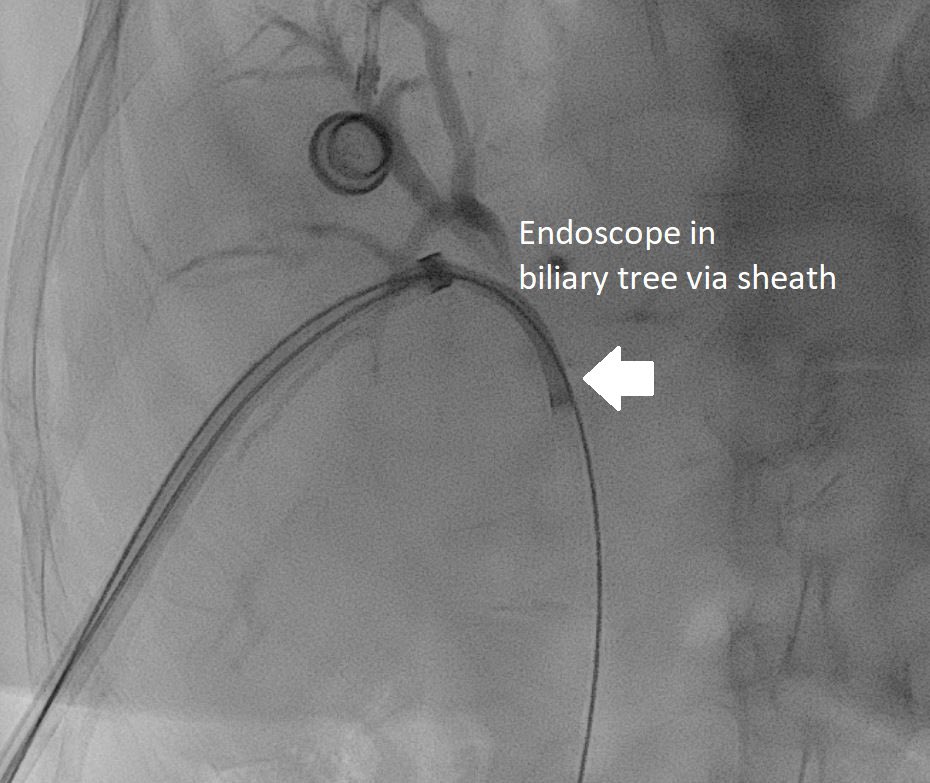

Cirrhotic patient with fundal varices and large PSS prior endoscopic flue injection now presented with massive upper GI bleed. Hb 6. Shunt occlusion with Double plugs - no further bleeds # Pinhole treatment for upper GI bleed @ISVIRIndia @No_cut_surgery @keithppereira @SRajesh_IR